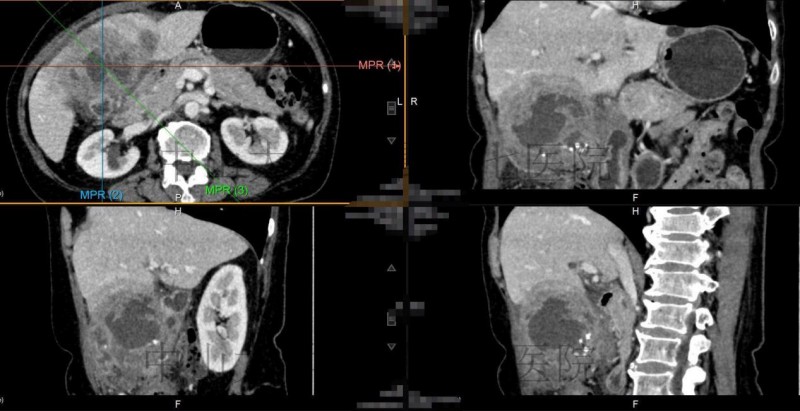

当值的医生给蔡奶奶做了一些常规检查,了解她的病史,觉得她的病情没那么简单,一度怀疑为胆囊癌症,采取消炎、止痛措施后,建议她做进一步检查,查明病因。经过CT检查、病理检查和多学科讨论,蔡奶奶被确诊为“黄色肉芽肿性胆囊炎”。原先并不起眼的胆囊炎经过多年的积累,“升级”成了与胆囊癌非常相似的大包块!中山七院普外科主任汤地介绍,“我们检索了国内外文献,黄色肉芽肿性胆囊炎较为罕见,临床表现与胆囊癌非常相似,公开报道的最大直径约15厘米,而这位患者在CT上测量最大直径足有16cm,几乎有菠萝那么大,需要尽快手术切除”。

胆囊的黄色肉芽肿块

7月25日,中山七院普外科团队为72岁的蔡奶奶顺利切除了16 X 10 cm的肿块,并应用ERAS加速康复理念,让蔡奶奶术后2天就能下床活动,一星期就出院了。“困扰了我二十多年的老毛病终于解决了”,蔡奶奶对这次手术十分满意。